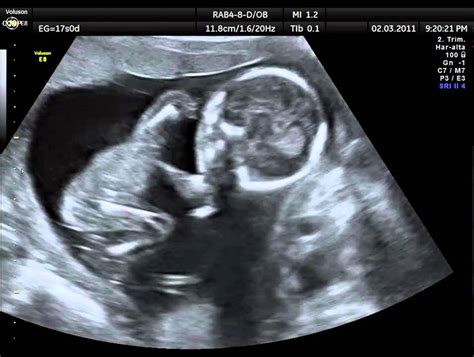

WebLa primera ecografía que se realiza a una embarazada ofrece datos muy interesantes sobre la gestación, aunque el embrión sea minúsculo. Detallamos a continuación los elementos que se identifican en las primeras ecografías, así como las etapas de. WebEsta semana tu bebé tiene el tamaño de un nabo pequeño. Ya mide casi 13 centímetros (5 pulgadas) y el cordón umbilical, por donde come y respira, está cada día más grueso y. WebEcografía de la semana 17 de embarazo: embrión de perfil. Se visualiza la órbita, la nariz y la boca. Asimismo se visualiza una parte del abdomen y la placenta arriba de la imagen.. WebA las 17 semanas de embarazo, una mujer debe visitar a un ginecólogo y pasar las pruebas necesarias. Incluyen pruebas de sangre y orina, pruebas hormonales. En la recepción,. WebEntre la semana 17 y 19 del embarazo verás a tu bebé crecidito: mide unos 15 centímetros y pesa alrededor de 200 gramos. Sus movimientos son cada vez. WebAbout Press Copyright Contact us Creators Advertise Developers Terms Privacy Policy & Safety How YouTube works Test new features Press Copyright Contact us Creators ... WebEl ecocardiograma fetal inicial suele realizarse entre las semanas 18 y 22 de gestación y puede repetirse según sea necesario a lo largo del embarazo. El estudio inicial suele.

WebEn la séptima semana de embarazo, es posible que la mujer ya empiece a notar el aumento de peso, además de otros síntomas característicos. El embrión sigue. WebEcografía de la semana 17 de embarazo: columna vertebral. En la imagen vemos la columna vertebral de feto donde se visualizan las vértebras cervicales, dorsales y.